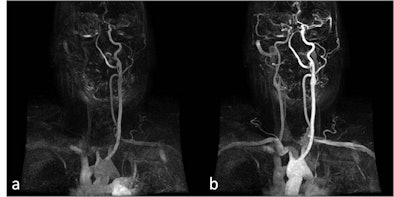

| Patient with dissection of brachiocephalic arterial trunk and right common carotid artery. A, B: Time-resolved sequences allow the visualization of an asymmetric transit time of the contrast agent, showing delayed opacification of right common and internal carotid artery compared to the normal left vessels. (Provided by Prof. Carlo Catalano and Dr. Beatrice Cavallo Marincola) |